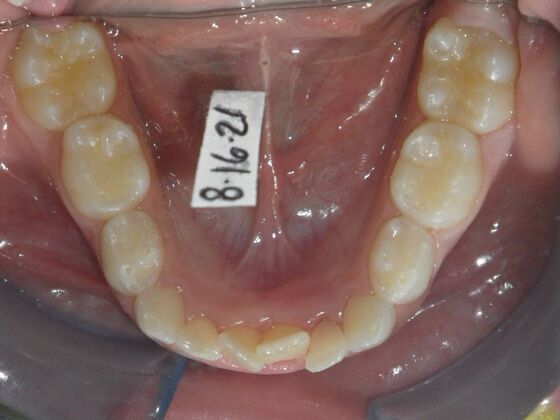

Patient presents with delayed eruption of the upper right central incisor and lower anterior crowding. Treatment plan to include exposure of right central incisor with bracket placement and correction of lower anterior crowding.